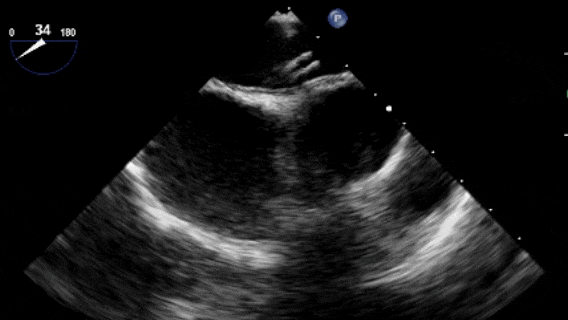

沿加硬導絲將9F輸送鞘送至左心房,退出導絲及輸送鞘內芯后,在超聲引導下送入1824PFO封堵器進行封堵。先釋放左盤面,整體回撤,緊貼房間隔,后釋放右盤面,進行推拉試驗,超聲在主動脈短軸切面、四腔心切面確認封堵器對二尖瓣等周圍組織無影響,位置及形態良好后釋放封堵器。撤出長鞘、縫合穿刺點后壓迫止血,加壓繃帶包扎,手術結束。

牽拉試驗

超聲觀察對周圍組織無影響

封堵器釋放后成型良好,無殘余分流